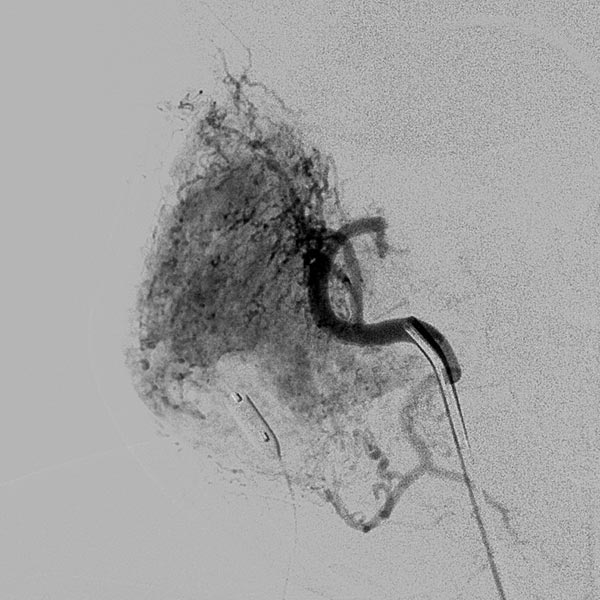

Digital subtraction angiography (DSA): After insertion of a 4F diagnostic catheter transarterially into the external carotid artery, selective advancement of a microcatheter into the maxillary artery. The infantile hemangioma presents as typical contrast pooling (“tumor blush”). The transvenously inserted balloon blocks the venous outflow and is clearly visible. Embolization was then carried out with particles of 150 micron size and without unintended venous outflow.

Control digital subtraction angiography (DSA) after first injection with particles. Part of the infantile hemangioma has already been occluded.

Digital subtraction angiography (DSA) after further super-selective injections with particles via a microcatheter while blocking the venous outflow. A good 50% of the infantile hemangioma has now been successfully occluded.

Digital subtraction angiography (DSA) after super-selective catheterization of the remaining arterial feeder supplying the infantile hemangioma.

During super-selective particle embolization (150 micron particles) via the arterial microcatheter after blocking out the venous outflow, the particles can be seen as a faintly contrasted area.